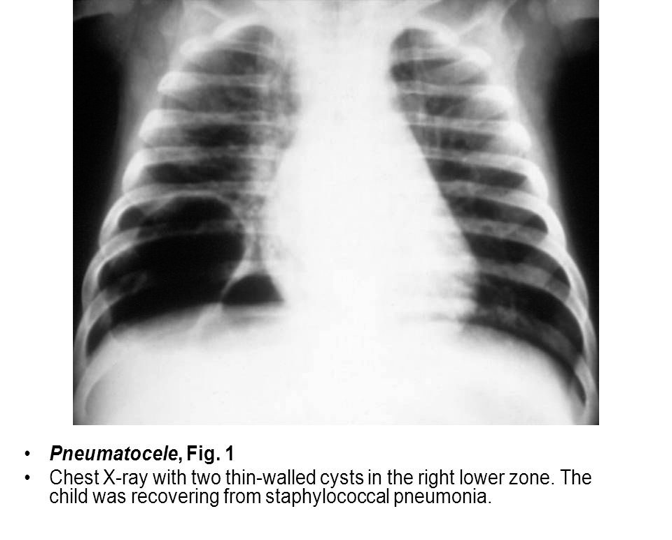

Pneumatocele :

Pneumatoceles are thin-walled, air-containing cysts of the lungs.